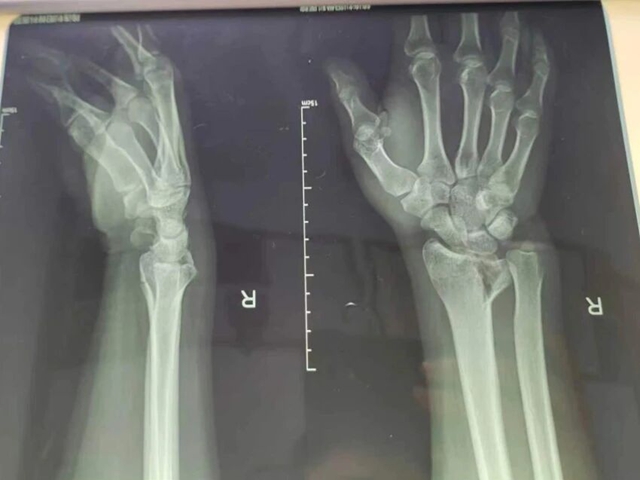

30余岁的李明(化名)在宜宾打球时不慎摔伤,双侧手臂当即疼痛难忍、无法动弹,当地医院检查提示双桡骨远端粉碎性骨折,经手法复位、石膏固定后仍疼痛难忍,为求进一步专业治疗,专程来到西南医科大学附属中医医院就诊。

复位前,患者影像资料